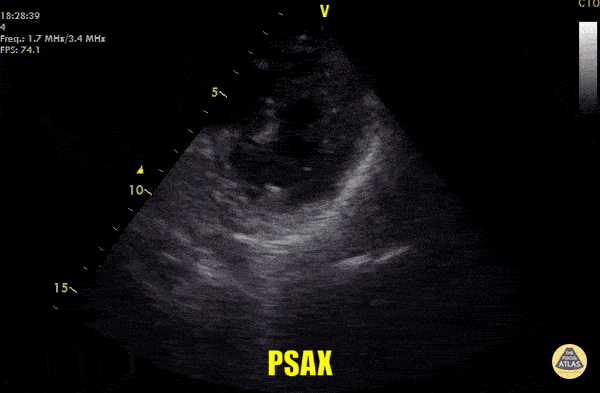

Left Ventricular Dysfunction - Asystole

Out of hospital arrest brought in by EMS. CPR had been ongoing for 20 minutes without ROSC. Parasternal short axis view at mid papillary level shows complete LV standstill once resuscitation was stopped, confirming the clinical diagnosis. Dr. Cian McDermott - Mater University Hospital Dublin, Ireland